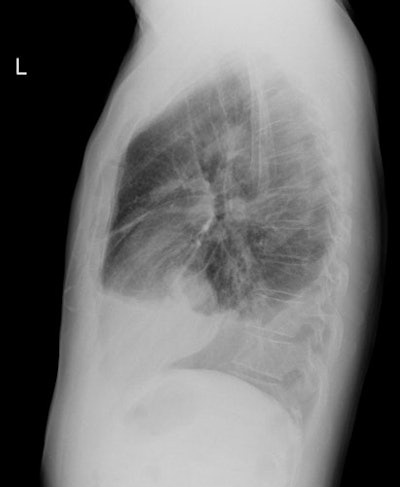

Computed tomography: Common findings include a unilateral pleural effusion, nodular pleural thickening, and interlobar fissure thickening [9]. Circumferential, nodular pleural thickening greater than 1 cm identified in over 90% of cases. Thickening extends into the interlobular fissure in about 85% of cases. Mediastinal pleural involvement is also seen. The absence of pleural thickening does not exclude malignancy, and cases of mesothelioma have been reported in which the only CT finding was a pleural effusion. Calcified pleural plaques are found in about 20% of patients and they may be engulfed by the tumor. Chest wall invasion may manifest as obscured fat planes, invasion of intercostal muscles, or rib destruction. Irregularity of the interface between the chest wall and the tumor is NOT a reliable indicator of chest wall invasion.

Mesothelioma on CT: The CT scan on the same patient shown above. The nodular mass-like pleural thickening is readily apparent on CT imaging. |